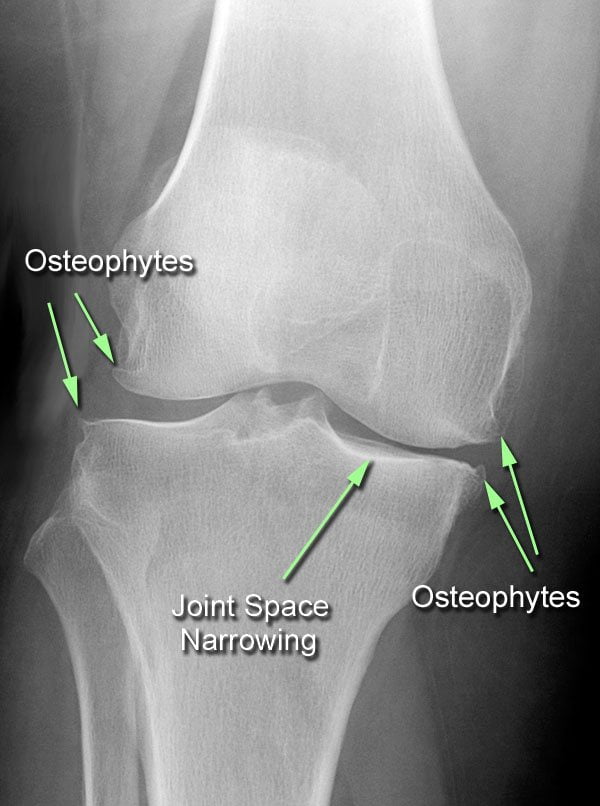

Все эти процессы сопровождаются воспалительной реакцией. Постепенно, если не лечиться, костные участки теряют хрящевой покров, что приводит к механическому раздражению, изнашиванию концевой костной поверхности, ее уплотнению, формированию костных наростов – остеофитов.

Осложняющий фактор неврологического заболевания – деформирующий артроз коленного сустава, когда при рентгенологическом обследовании наблюдается заметное разрастание костных наростов (остеофитов) на суставной поверхности.